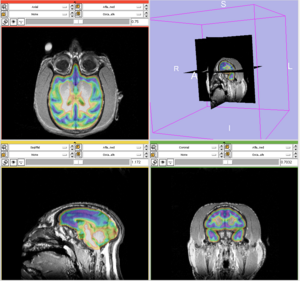

- The results for the best and worst segmentations are shown in the following. For each subject, the first figure shows the alignment of Gray matter atlas (these will be changed to checker board figures aligning target and the whole brain atlas soon) with the brains, and the second figure shows the segmentation results.

Best Segmentation: Oscar